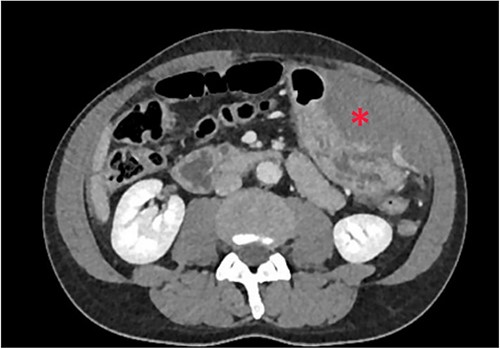

The patient was pale, hemodynamically stable, and with signs of peritoneal irritation. His hemoglobin was 15.1 g/dL. Contrast enhanced CT demonstrated 11.6 × 8.8 × 16.5 cm3 intramural hematoma in anterior stomach wall with active bleeding and hemoperitoneum (Figs 2 and 3). Exploratory laparotomy was done after optimizing the patient.